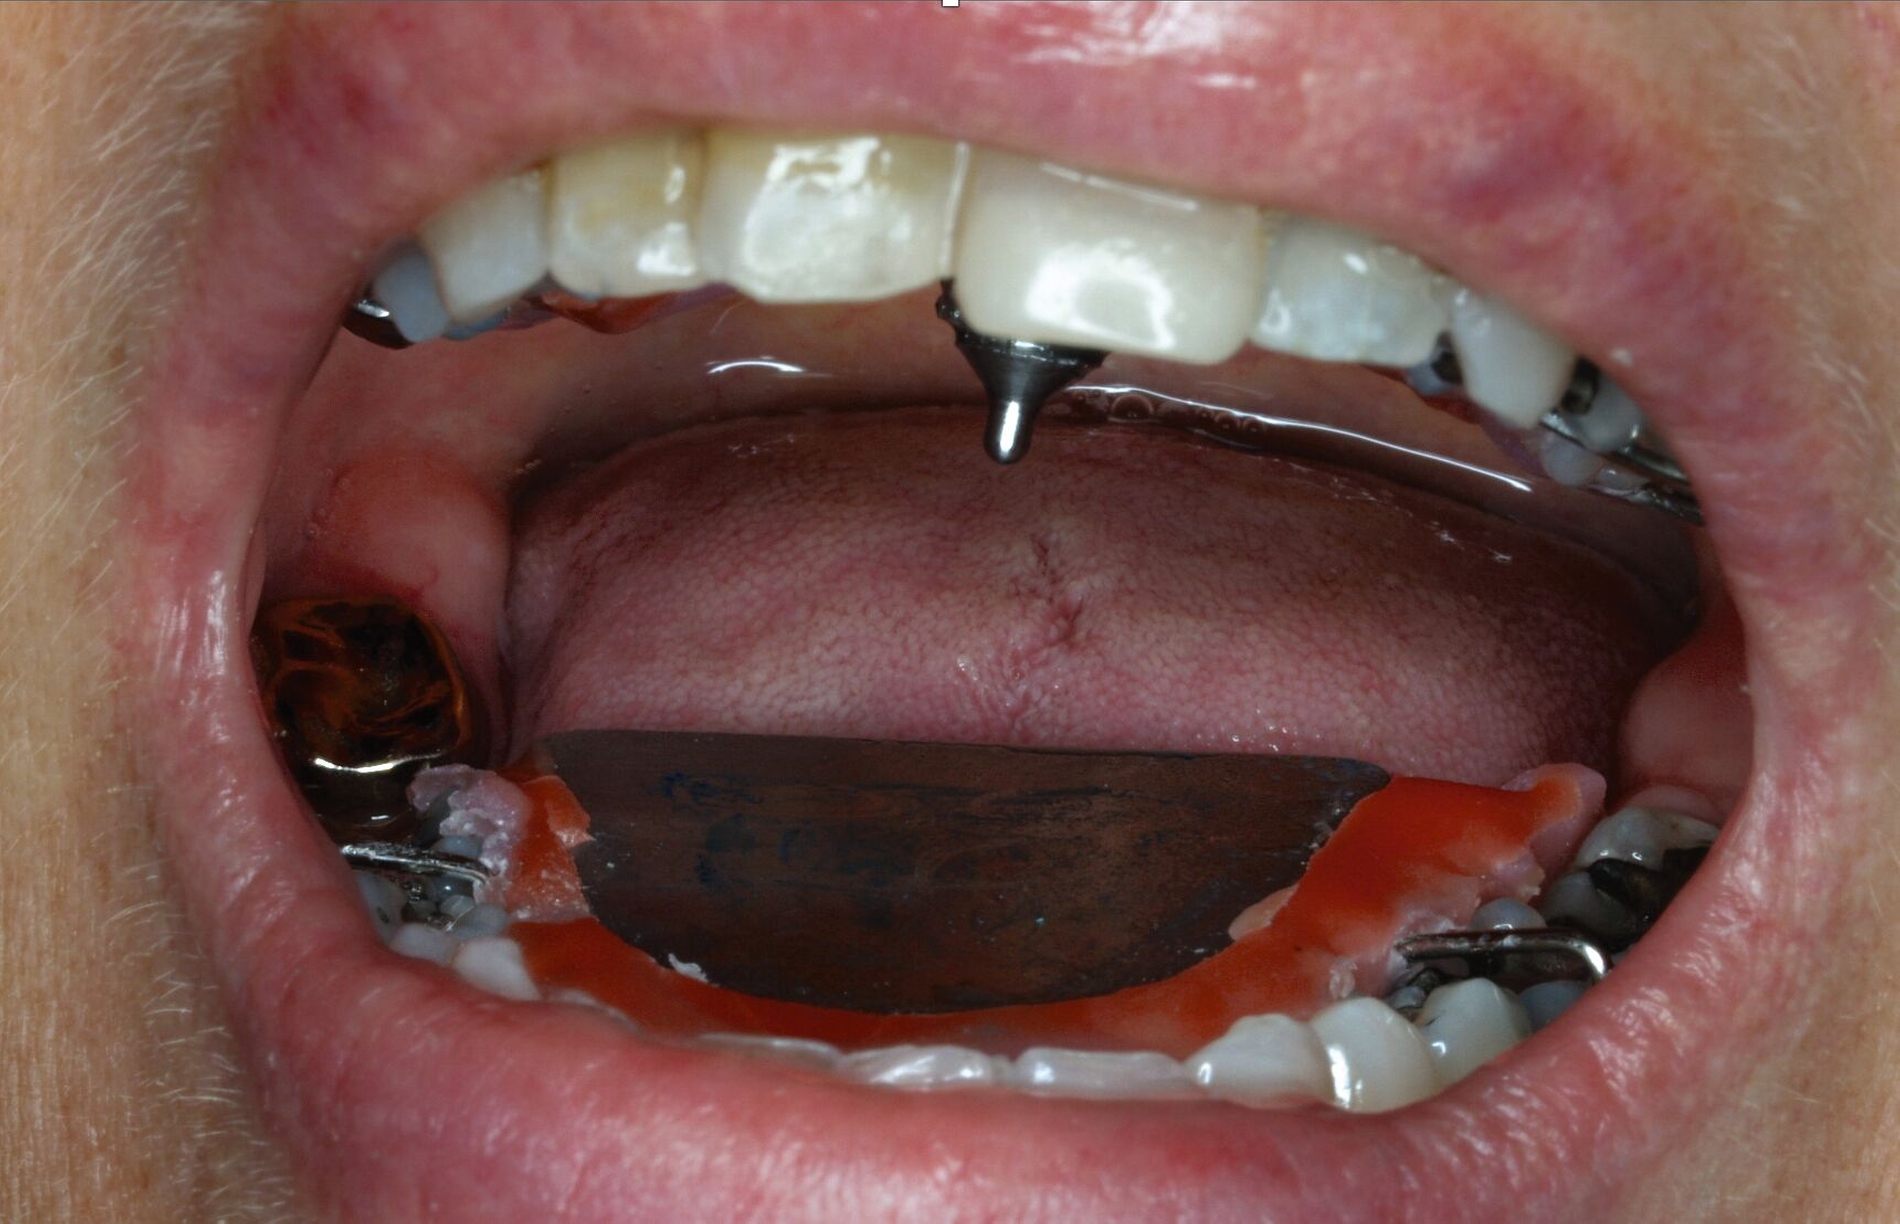

Klinisch zeigten sich diverse großflächig, mehrheitlich mit Amalgam gefüllte Seitenzähne, suffiziente endodontische Behandlungen an den Zähnen 16 und 14 sowie intakte Kronen an den Zähnen 16 und 48 (Abbildung 2). Ein Parodontaler Screening-Index (PSI) wurde erhoben (1-1-0-0-2-1), der stabile Verhältnisse nachwies. Das funktionelle CMD-Screening zeigte eine nicht-druckdolente Kaumuskulatur sowie eine uneingeschränkte Mundöffnung ohne Reiben und Knacken.

Tabelle 1 zeigt das entsprechende Befundschema mit den Taschentiefen mesial und distal, den Lockerungsgraden und den Sensibilitätsüberprüfungen mittels Kältespray (ViPr). Die Ruheschwebelage wurde mithilfe des Zielinsky-Zirkels auf 2 mm bestimmt. Die Nonokklusion im Seitenzahnbereich konnte auf circa 1,5 mm bemessen werden. Tabelle 2 spiegelt das entsprechende Okklusionsprotokoll wider. Das Okklusionsprofil wird auch in den Abbildungen 3a bis 3c deutlich.